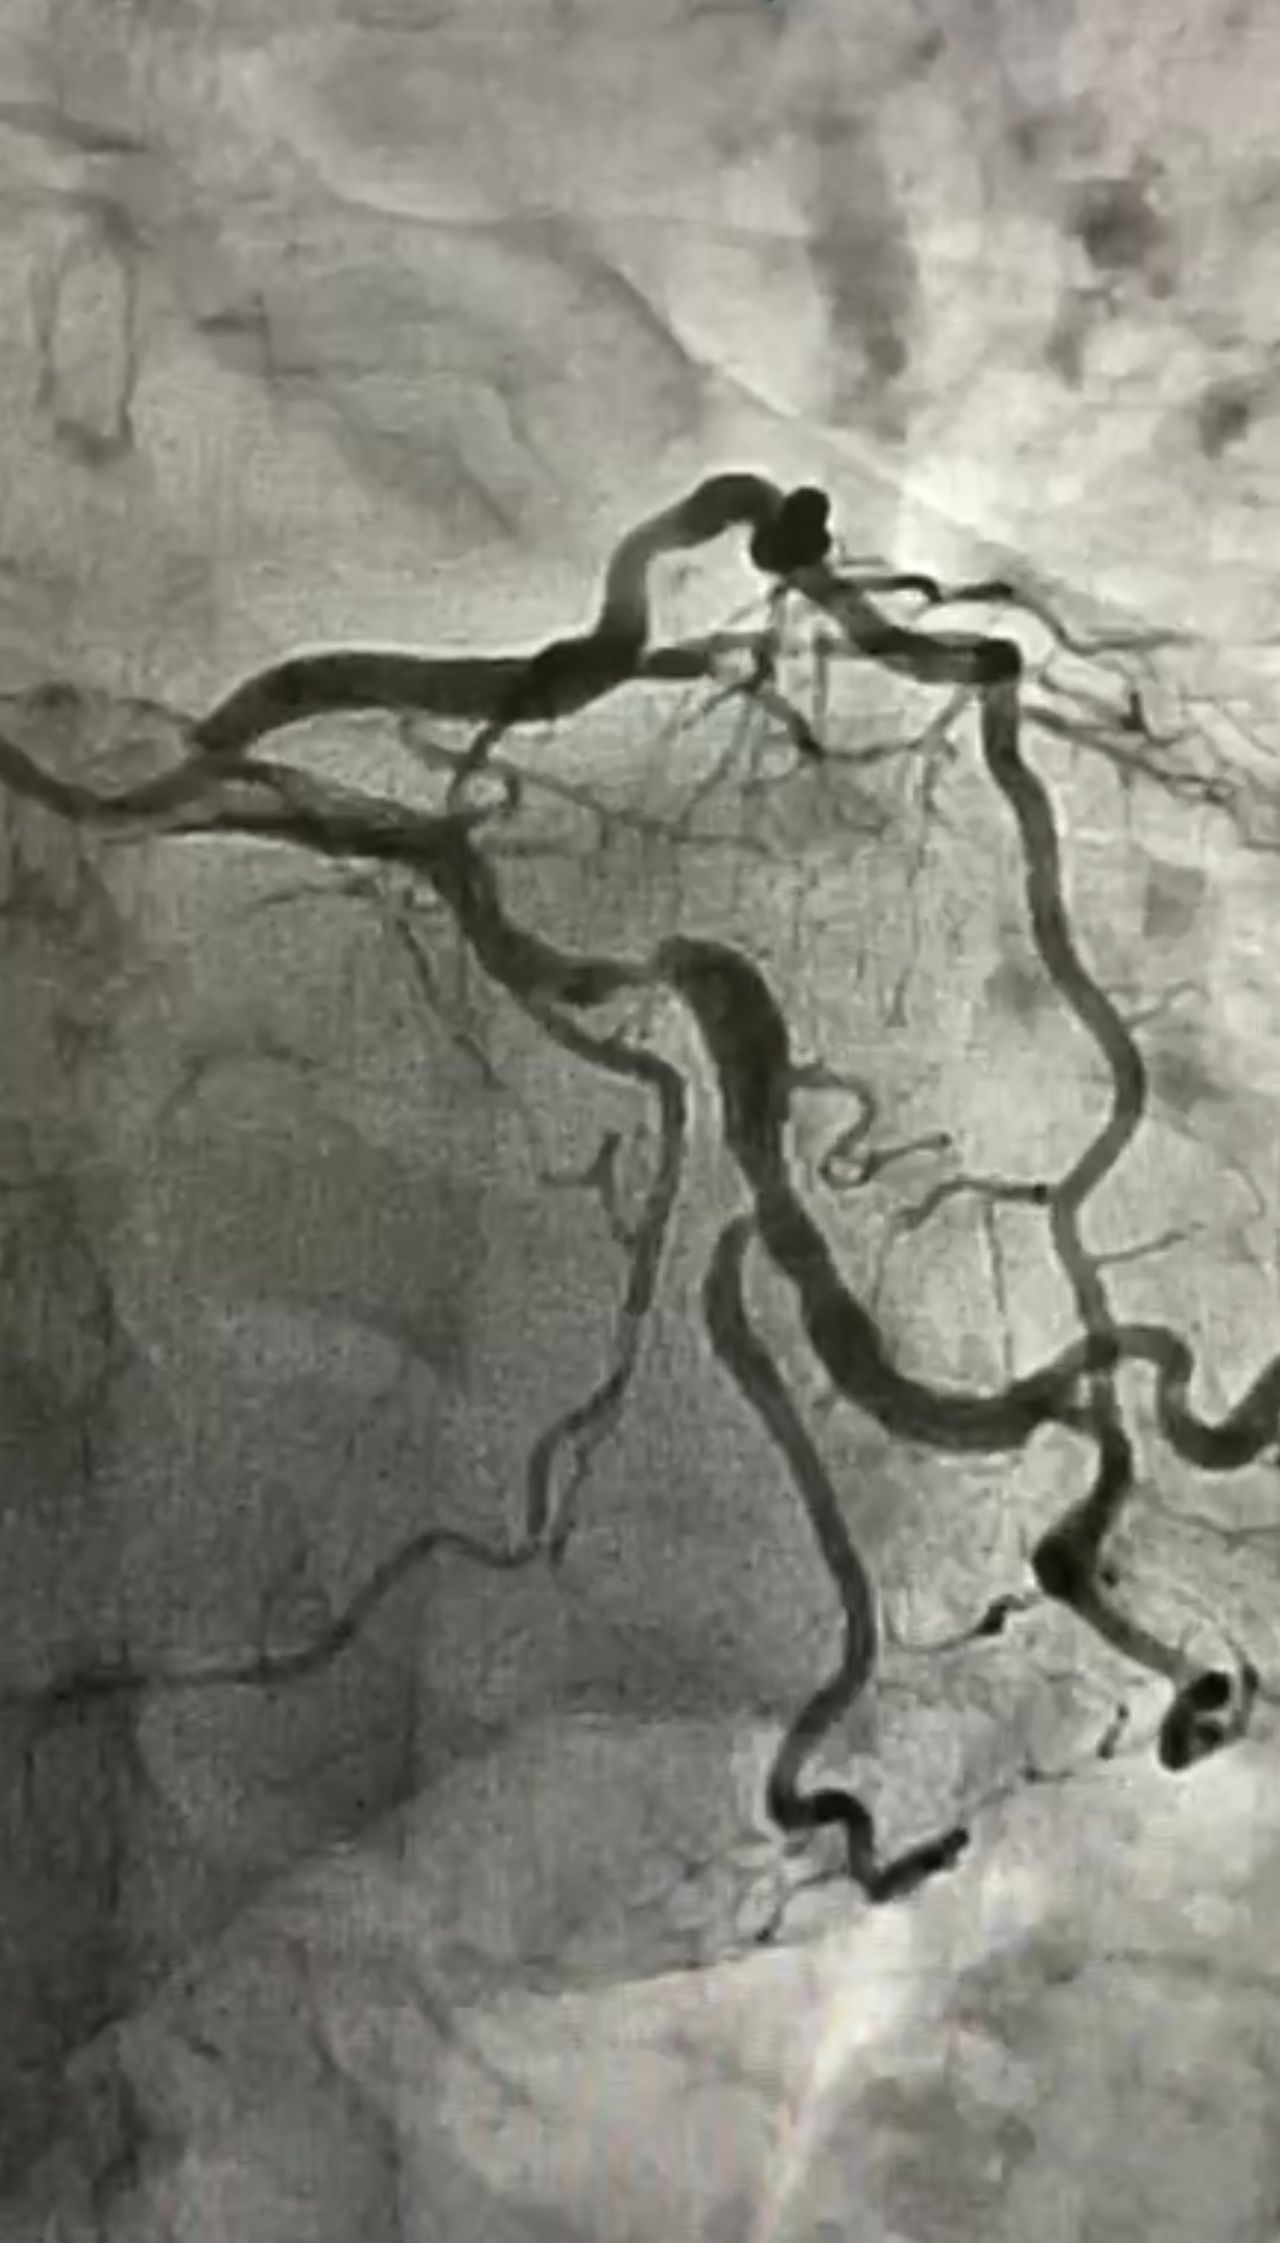

• Cardiopatia ischemica e angina

Seguo chi presenta dolore al petto o cardiopatia ischemica con un approccio pratico e rassicurante. Valuto i sintomi, imposto la terapia adeguata e decido insieme al paziente se sono necessari esami più approfonditi.